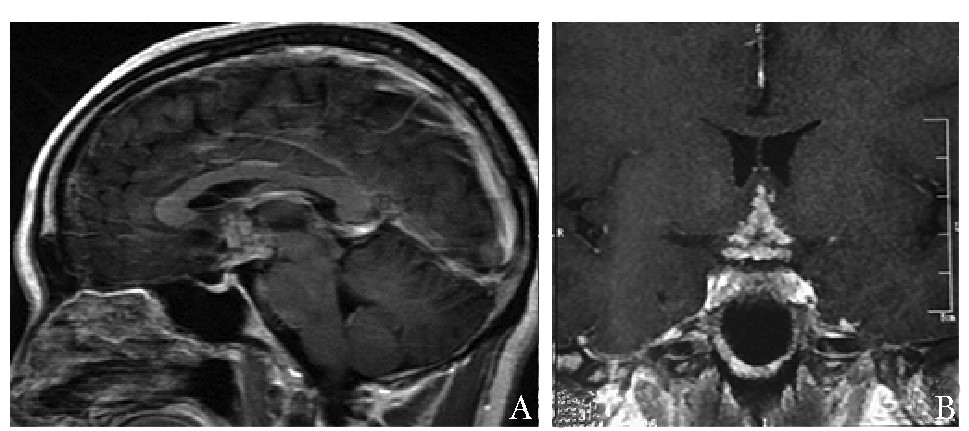

• 摘要: 建立正确的临床思维是提升临床能力的核心和根本,是医学教育的重点及难点。与常见病不同,垂体疾病作为一种罕见病,其临床思维具有其独特性。本文以一例下丘脑垂体多发占位为例,从资料搜集、逻辑推理、循证教学、多科讨论、基础医学研究等方面总结罕见病诊断思维特点,以期提高临床医师的工作效率,并为垂体疾病的临床思维训练提供相关经验。

Abstract: Establishing correct clinical thinking is the core and foundation of improving doctors' clinical ability as well as the key and difficult point of medical education. Different from common diseases, clinical thinking about pituitary diseases has its unique characteristics as a rare disease. Taking a case of Hypothalamic and pituitary mass as an example, this paper summarized the characteristics of diagnosis thinking of rare diseases from the aspects of data collection, logical reasoning, evidence-based teaching, multiple disciplinary teams, and basic medical research, to improve the efficiency of physicians and provide experience for the training of clinical thinking about pituitary diseases.